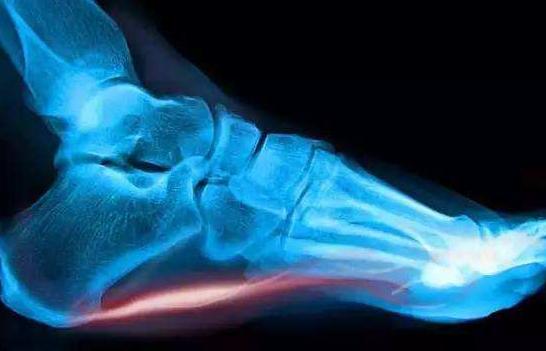

(1)足底部筋膜炎

足底部筋膜炎所致的脚后跟疼约占患者的80%,是第一主因。它导致的脚后跟疼有如下特点:

- 早晨下床或静止一段时间后,足跟着地站立时感到足跟部疼痛;

- 最初迈步时疼痛加剧,行走数步后有所缓解;

- 随着步行距离或站立时间的增加,疼痛会再次加剧。